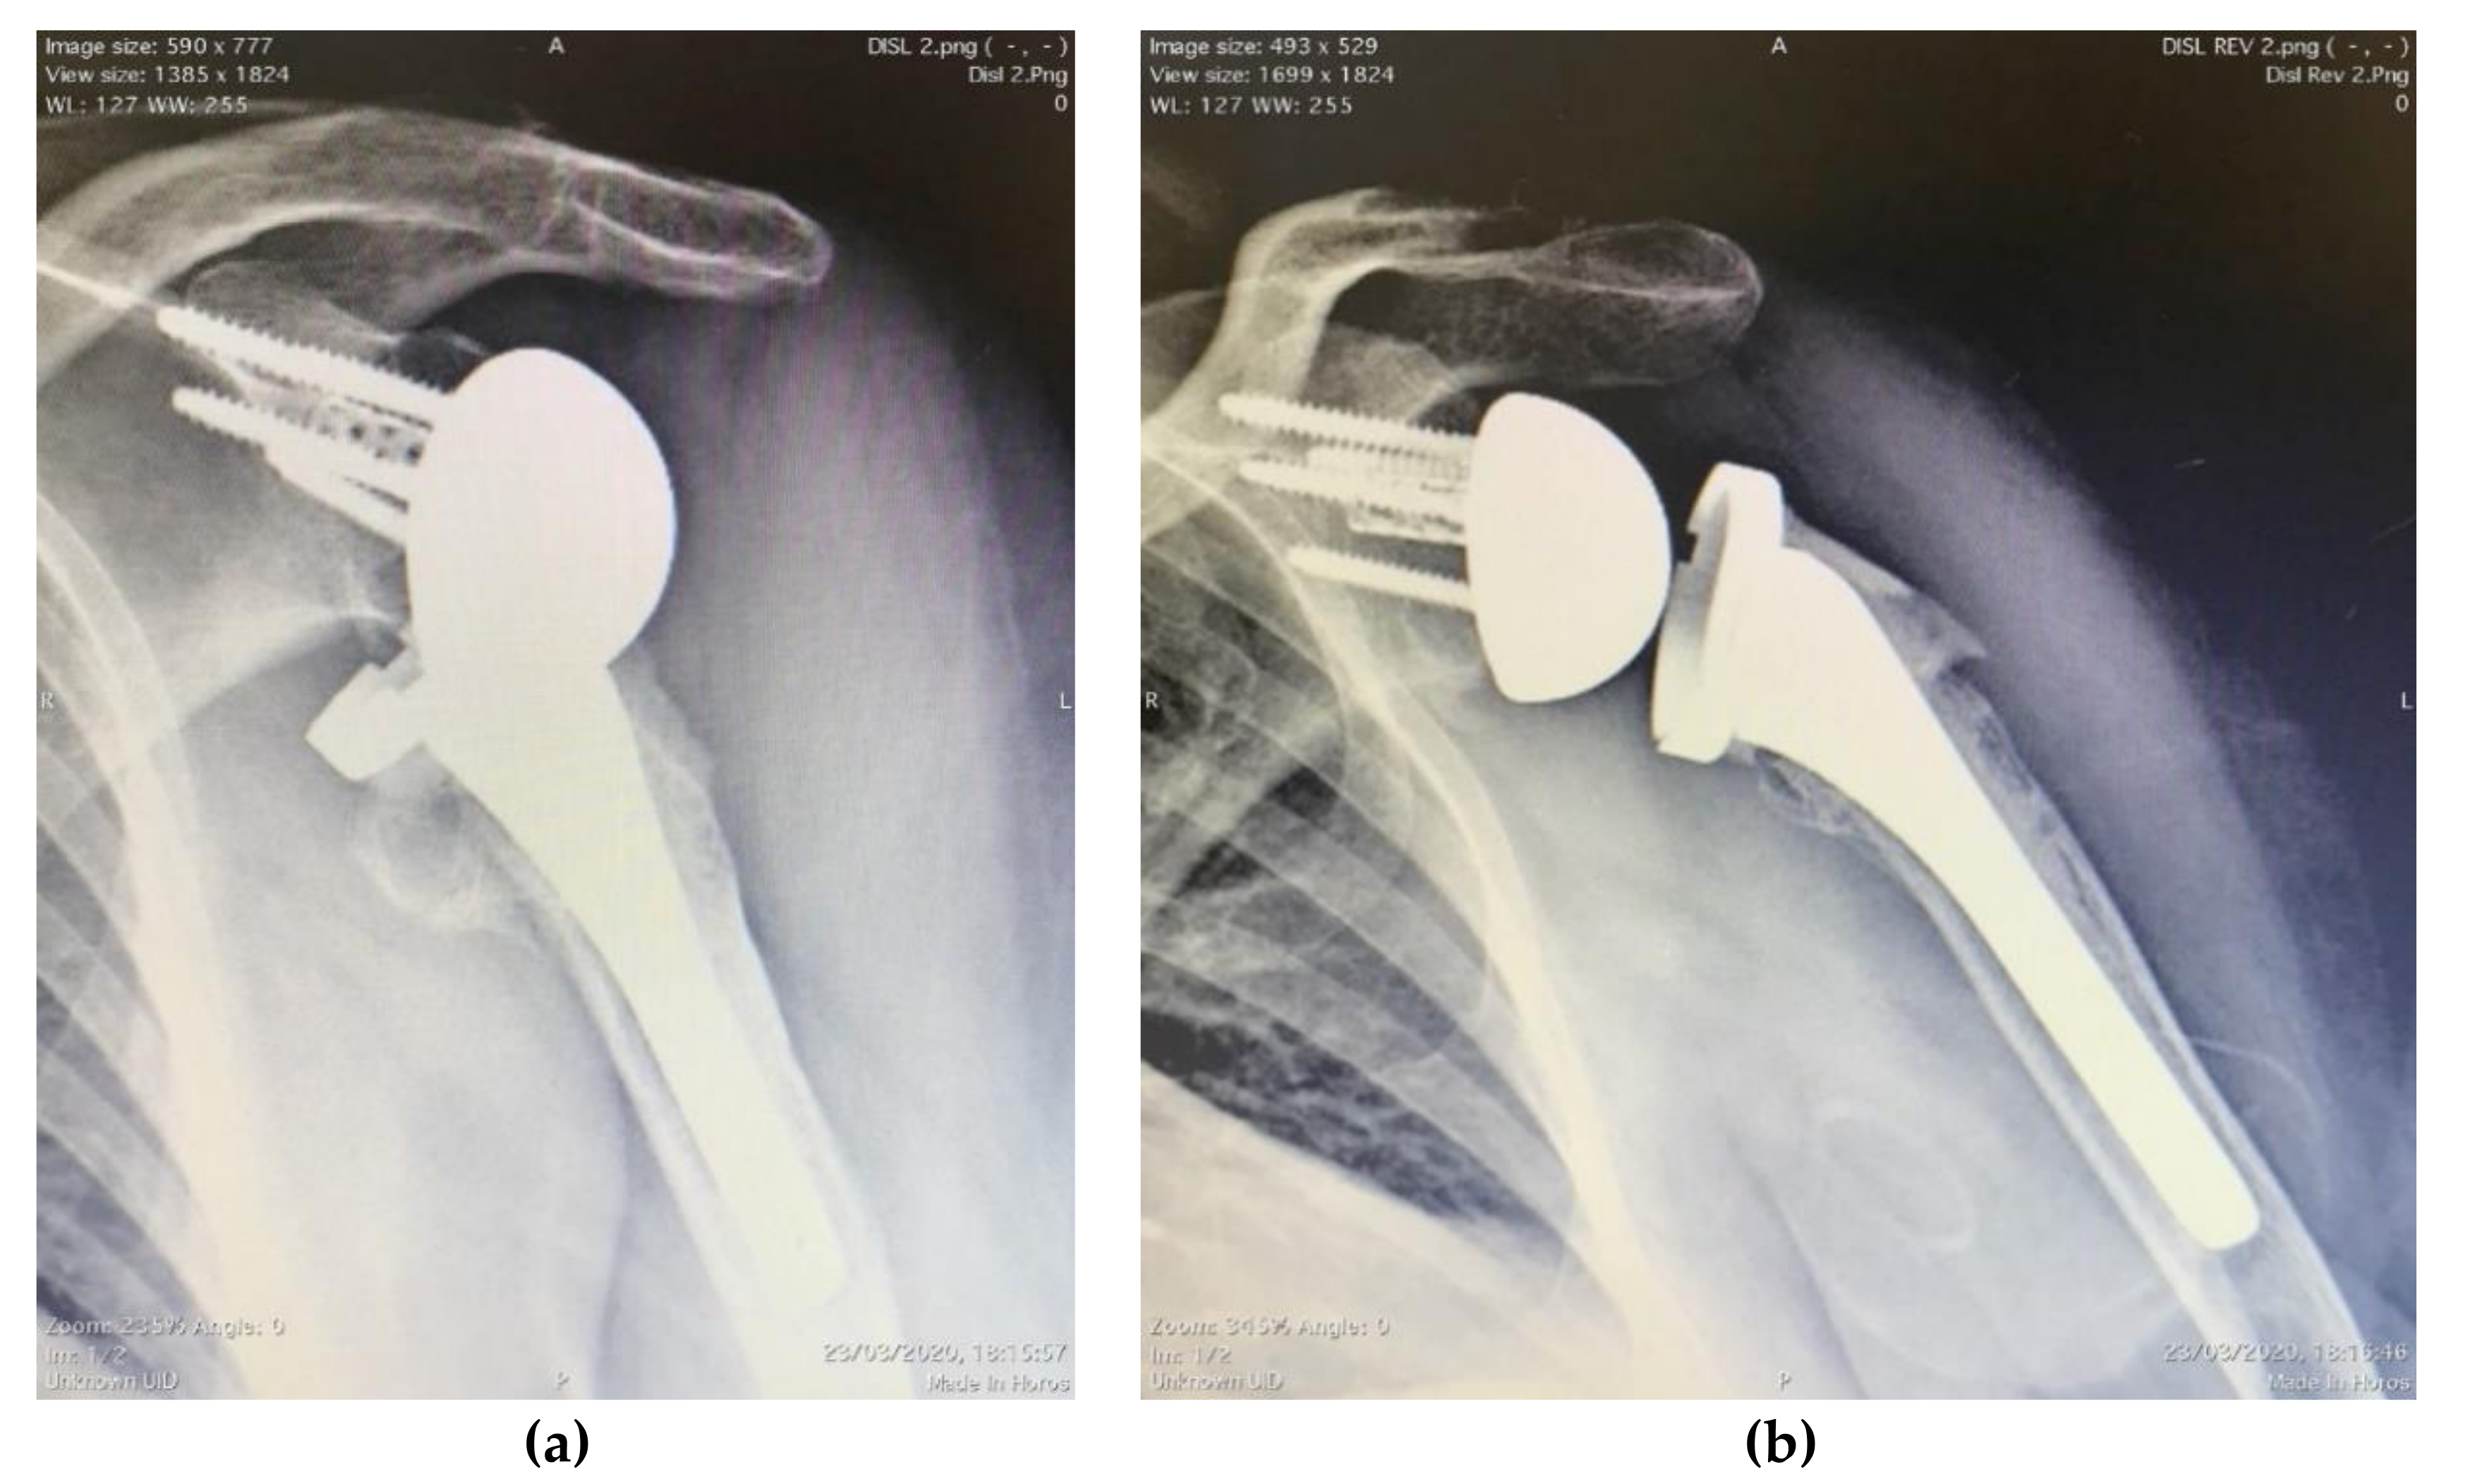

3.2. Radiographic

3.3. Complications